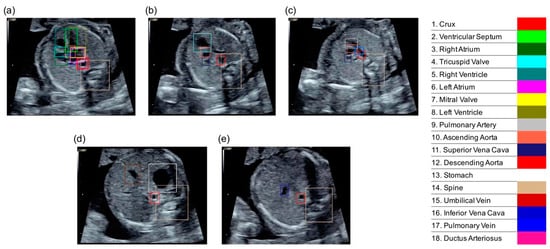

2.2. Cardiac Substructure Detection

2.3. Visualization of the Detection Result